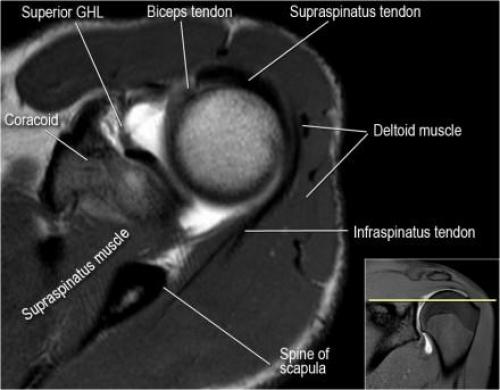

Хилл-Сакса мрт. Нормальная анатомия плечевого сустава в аксиальных изображениях и контрольный список.

- обратите внимание на верхние отделы суставной губы и прикрепление верхней плече-лопаточной связки. На данном уровне ищется SLAP-повреждение (Superior Labrum Anterior to Posterior) и варианты строения в виде отверстия под сутавной губой (sublabral foramen - подгубное отверстие). На этом же уровне по задне-боковой поверхности головки плечевой кости визуализируются повреждение Хилл-Сакса.

- уровень средней плече-лопаточной связки и передних отделов суставной губы. Поищите комплекс Буффорда. Изучите хрящи.

- вогнутость заднебокового края головки плечевой кости не следует путать с повреждением Хилл-Сакса, поскольку это нормальная форма для данного уровня. Повреждение Хилл-Сакса визуализируется только на уровне клювовидного отростка. В предних отделах мы сейчас на урвоне 3-6 часов. Здесь визуализируются повреждение Банкарта и его варианты.

- обратите внимание на волокна нижней плече-лопаточной связки. На данном уровне так же ищется повреждение Банкарта.